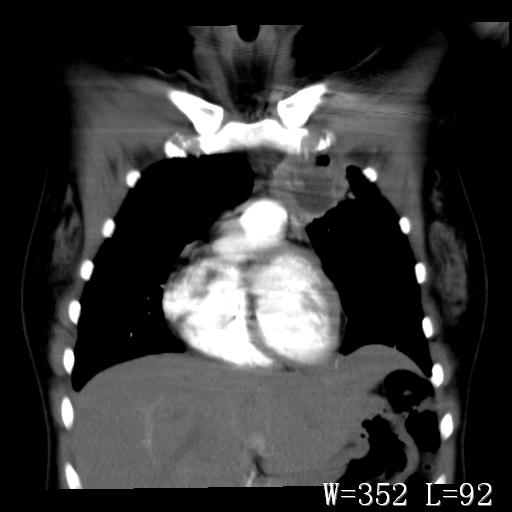

标题: CT27017:1、肺结核?2、永存左上腔静脉。

女,32岁,自述肺结核治疗多年复查。

1)考虑左肺上叶肺脓肿,节段性肺不张。2)永存左上腔静脉。

1)考虑左肺上叶节段性肺不张。原因?2)永存左上腔静脉。

考虑左肺上叶胸腺瘤可能性大。肺不张/永存左上腔静脉

1、胸骨后偏左侧囊实性病灶,考虑胸腺瘤可能性大。2、永存左上腔静脉。